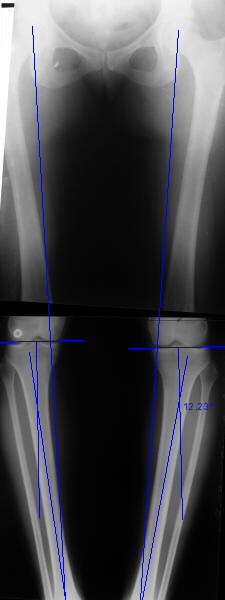

Re: Деформация голеней

This is a case of tibia vara and the cora is well down as you can see on the sketch, so do a percut otm on the cora and just nail it with an entry point medially to the tubercle and do an extra proximal antero-posterior interference screw if needed.